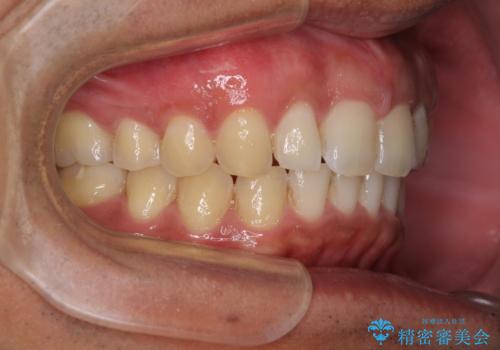

- 上顎前歯の突出感とすきっ歯を気にして来院された患者様です。

奥歯の咬み合わせを見ると、下顎に対して上顎が前方に位置していたため、補助装置により上顎歯列全体を後方に移動させ、その後インビザラインにて歯列全体を整えることとしました。